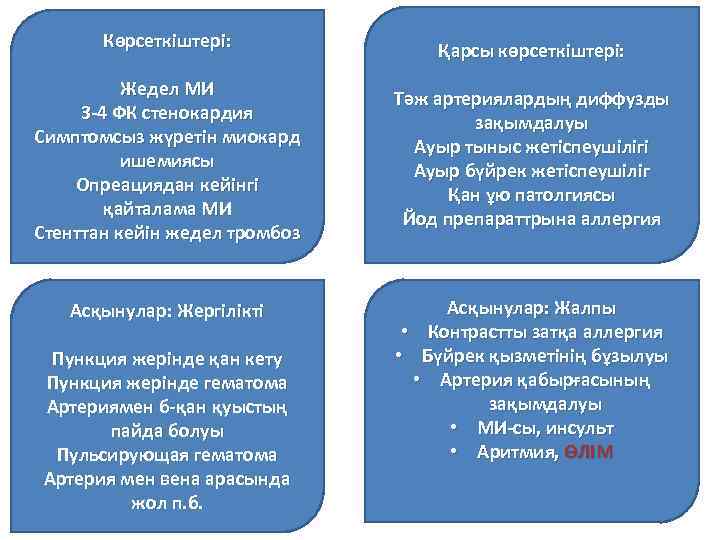

Көрсеткіштері: Жедел МИ 3 -4 ФК стенокардия Симптомсыз жүретін миокард ишемиясы Опреациядан кейінгі қайталама МИ Стенттан кейін жедел тромбоз Асқынулар: Жергілікті Пункция жерінде қан кету Пункция жерінде гематома Артериямен б-қан қуыстың пайда болуы Пульсирующая гематома Артерия мен вена арасында жол п. б. Қарсы көрсеткіштері: Тәж артериялардың диффузды зақымдалуы Ауыр тыныс жетіспеушілігі Ауыр бүйрек жетіспеушіліг Қан ұю патолгиясы Йод препараттрына аллергия Асқынулар: Жалпы • Контрастты затқа аллергия • Бүйрек қызметінің бұзылуы • Артерия қабырғасының зақымдалуы • МИ-сы, инсульт • Аритмия, ӨЛІМ

Көрсеткіштері: Жедел МИ 3 -4 ФК стенокардия Симптомсыз жүретін миокард ишемиясы Опреациядан кейінгі қайталама МИ Стенттан кейін жедел тромбоз Асқынулар: Жергілікті Пункция жерінде қан кету Пункция жерінде гематома Артериямен б-қан қуыстың пайда болуы Пульсирующая гематома Артерия мен вена арасында жол п. б. Қарсы көрсеткіштері: Тәж артериялардың диффузды зақымдалуы Ауыр тыныс жетіспеушілігі Ауыр бүйрек жетіспеушіліг Қан ұю патолгиясы Йод препараттрына аллергия Асқынулар: Жалпы • Контрастты затқа аллергия • Бүйрек қызметінің бұзылуы • Артерия қабырғасының зақымдалуы • МИ-сы, инсульт • Аритмия, ӨЛІМ